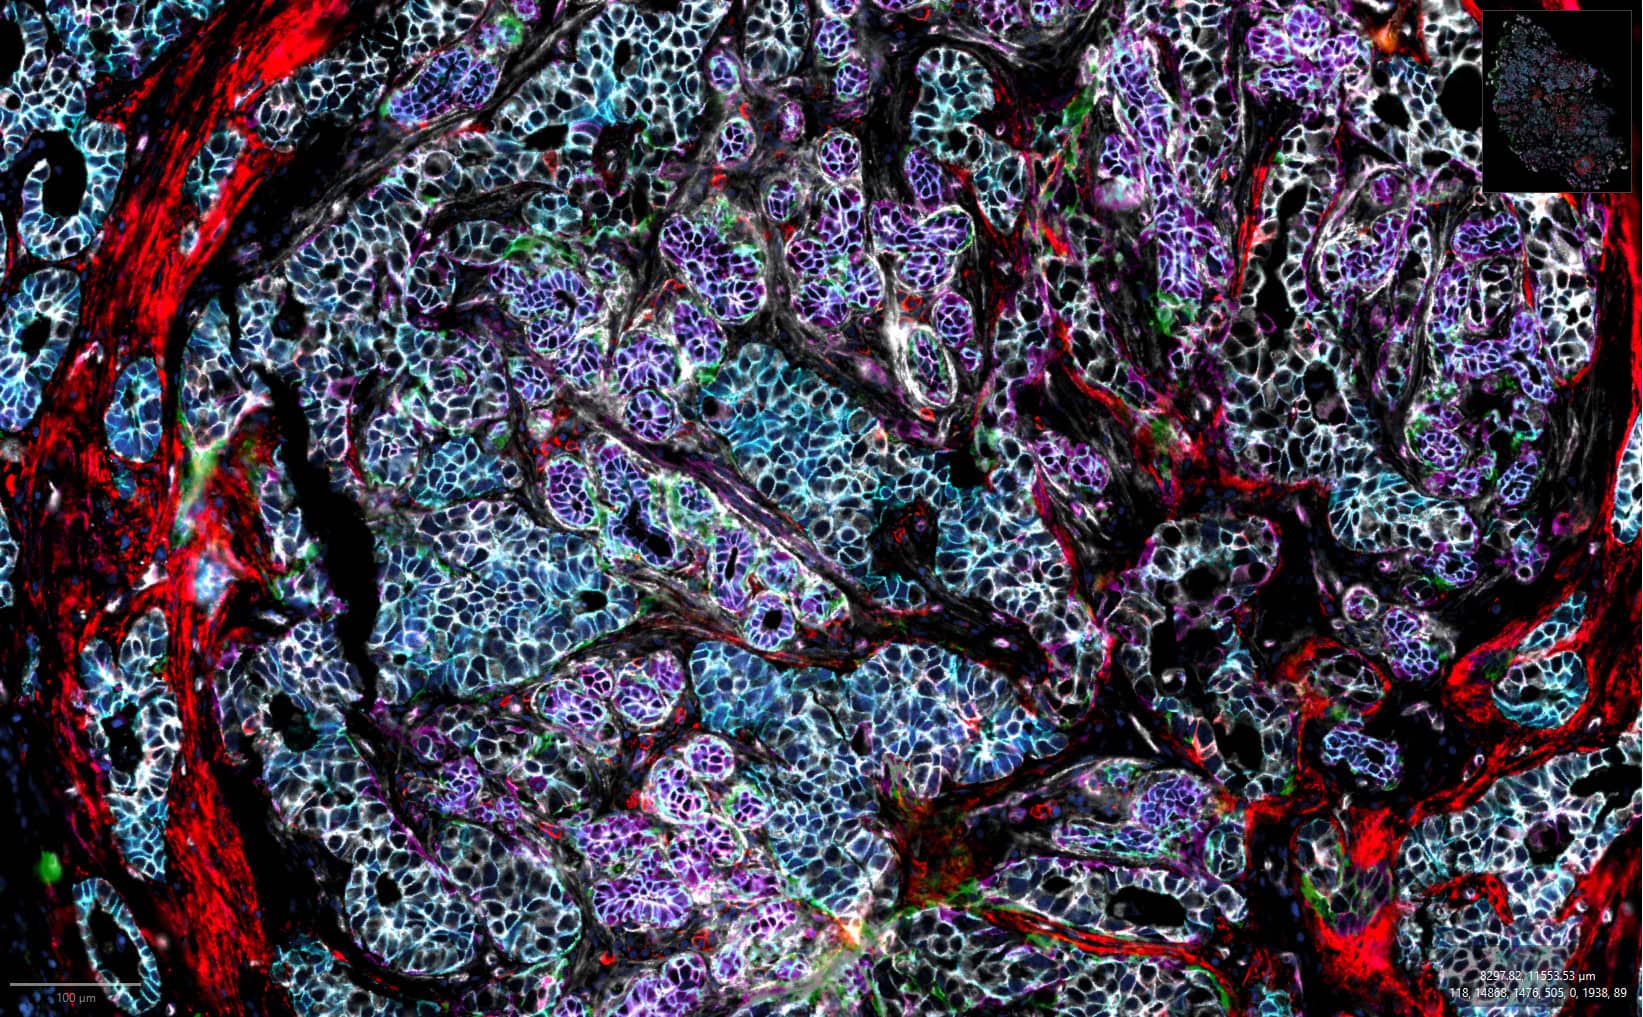

By combining 182 nm/pixel resolution, an 8-log dynamic range, and whole-slide imaging across more than 700 mm² of tissue, the CellScape XR platform enables confident identification of rare cell populations, accurate discrimination between low and high expressors, and precise phenotypic classification at single-cell and subcellular resolution.

High-resolution imaging for precise single-cell phenotyping across complex tissues

CellScape PSP delivers market-leading spatial proteomics, capturing the widest dynamic range of protein expression per cell while maintaining single-cell resolution across complex tissues. This high-resolution, high- dynamic-range imaging ensures accurate detection of low-, mid-, and high-expressing biomarkers, enabling confident single-cell phenotyping and robust quantitative insights

FFPE Breast Cancer

HDR Composite